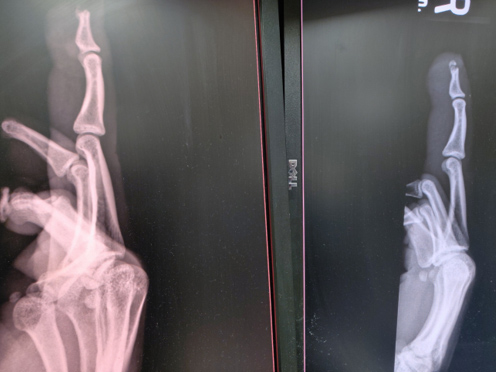

After reviewing the X-ray at bedside, emergency department physician proceeded with repair of the tissue. The amputation had left the nail intact as you can see on the lateral X-ray.

X-ray images taken before (left) and after (right) the repair: